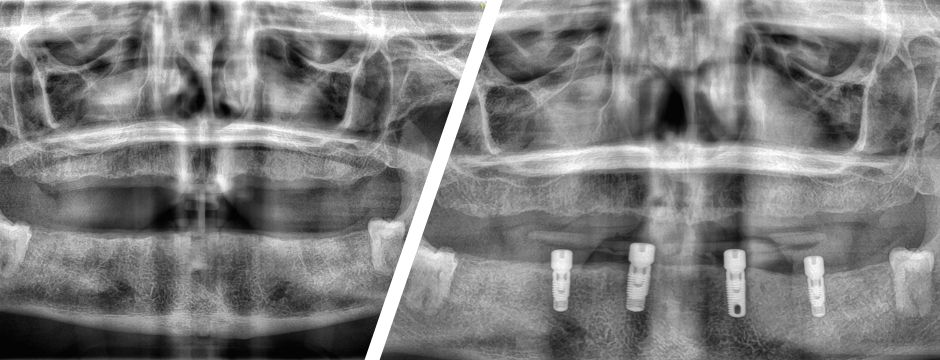

Implant Supported Dentures

Implant Overdenture Before and After